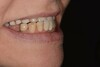

La patiente a moins de 50 ans et se présente au cabinet d’implantologie pour se faire poser des implants au maxillaire et ne plus porter de prothèses amovibles.

Le menton de la patiente est légèrement proéminent.

Les dents de la prothèse du haut viennent « en face » des dents du bas (en bout-à-bout) alors qu’elles devraient être à l’extérieur et circonscrire les dents du bas. Le visage de la patiente est légèrement affaissé (perte de dimension verticale).